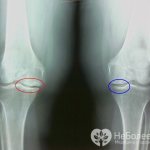

В основе гонартроза лежит патологический процесс разрушения суставного хряща, с которым связаны клинические и рентгенологические проявления болезни, а именно боль, ограничение подвижности в суставе, сужение суставной щели, остеофиты.

- значительное сужение суставной щели и разрастание остеофитов.

Рентгенография

Общепринятым в диагностике заболевания в настоящее время остается рентгенологический метод. Однако степень деструктивного поражения суставного хряща не соотносится с рентгенологической стадией гонартроза, хотя корреляция между ними усиливается при наличии синовита.

Поэтому на ранних стадиях дегенеративных поражений сочленений, когда изменения в костной ткани еще незначительны, рентгенологический метод исследования малоинформативен.